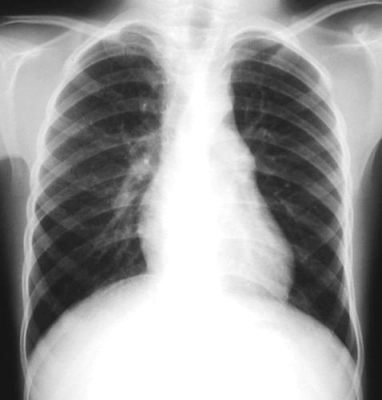

Radiografía del tórax

Radiologia PA Pre-operatoria

Rx. Torax PA. Radiotransparencia conservada en ambos campos pulmonares, sin infiltrados parenquimatosos, hileo y patrón de flujo pulmonar normal, senos costo y cardio-diafragmaticos libres, silueta cardio-mediastinica en posicion y morfologia normal aunque puede notarse el boton aortico borroso, mal definido; El esqueleto y partes blandas sin alteraciones.